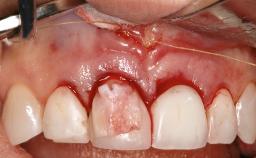

Treatment of Peri-Implantitis at a Zirconia Implant

Due to their promising clinical performance, zirconia implants have recently become popular alternatives to titanium implants, particularly for areas with high esthetic demands (Holländer and coworkers 2016; Roehling and coworkers 2016; Lorenz and coworkers 2019). However, regardless of the reported high survival and success rates, zirconia implants were affected by peri-implant diseases over the short observation period, suggesting the importance of treating peri-implant diseases at zirconia implants (Becker and coworkers 2017). In their case, Frank Schwarz and Ausra Ramanauskaite present 3-year results following mechanical debridement alongside Er:YAG laser monotherapy.